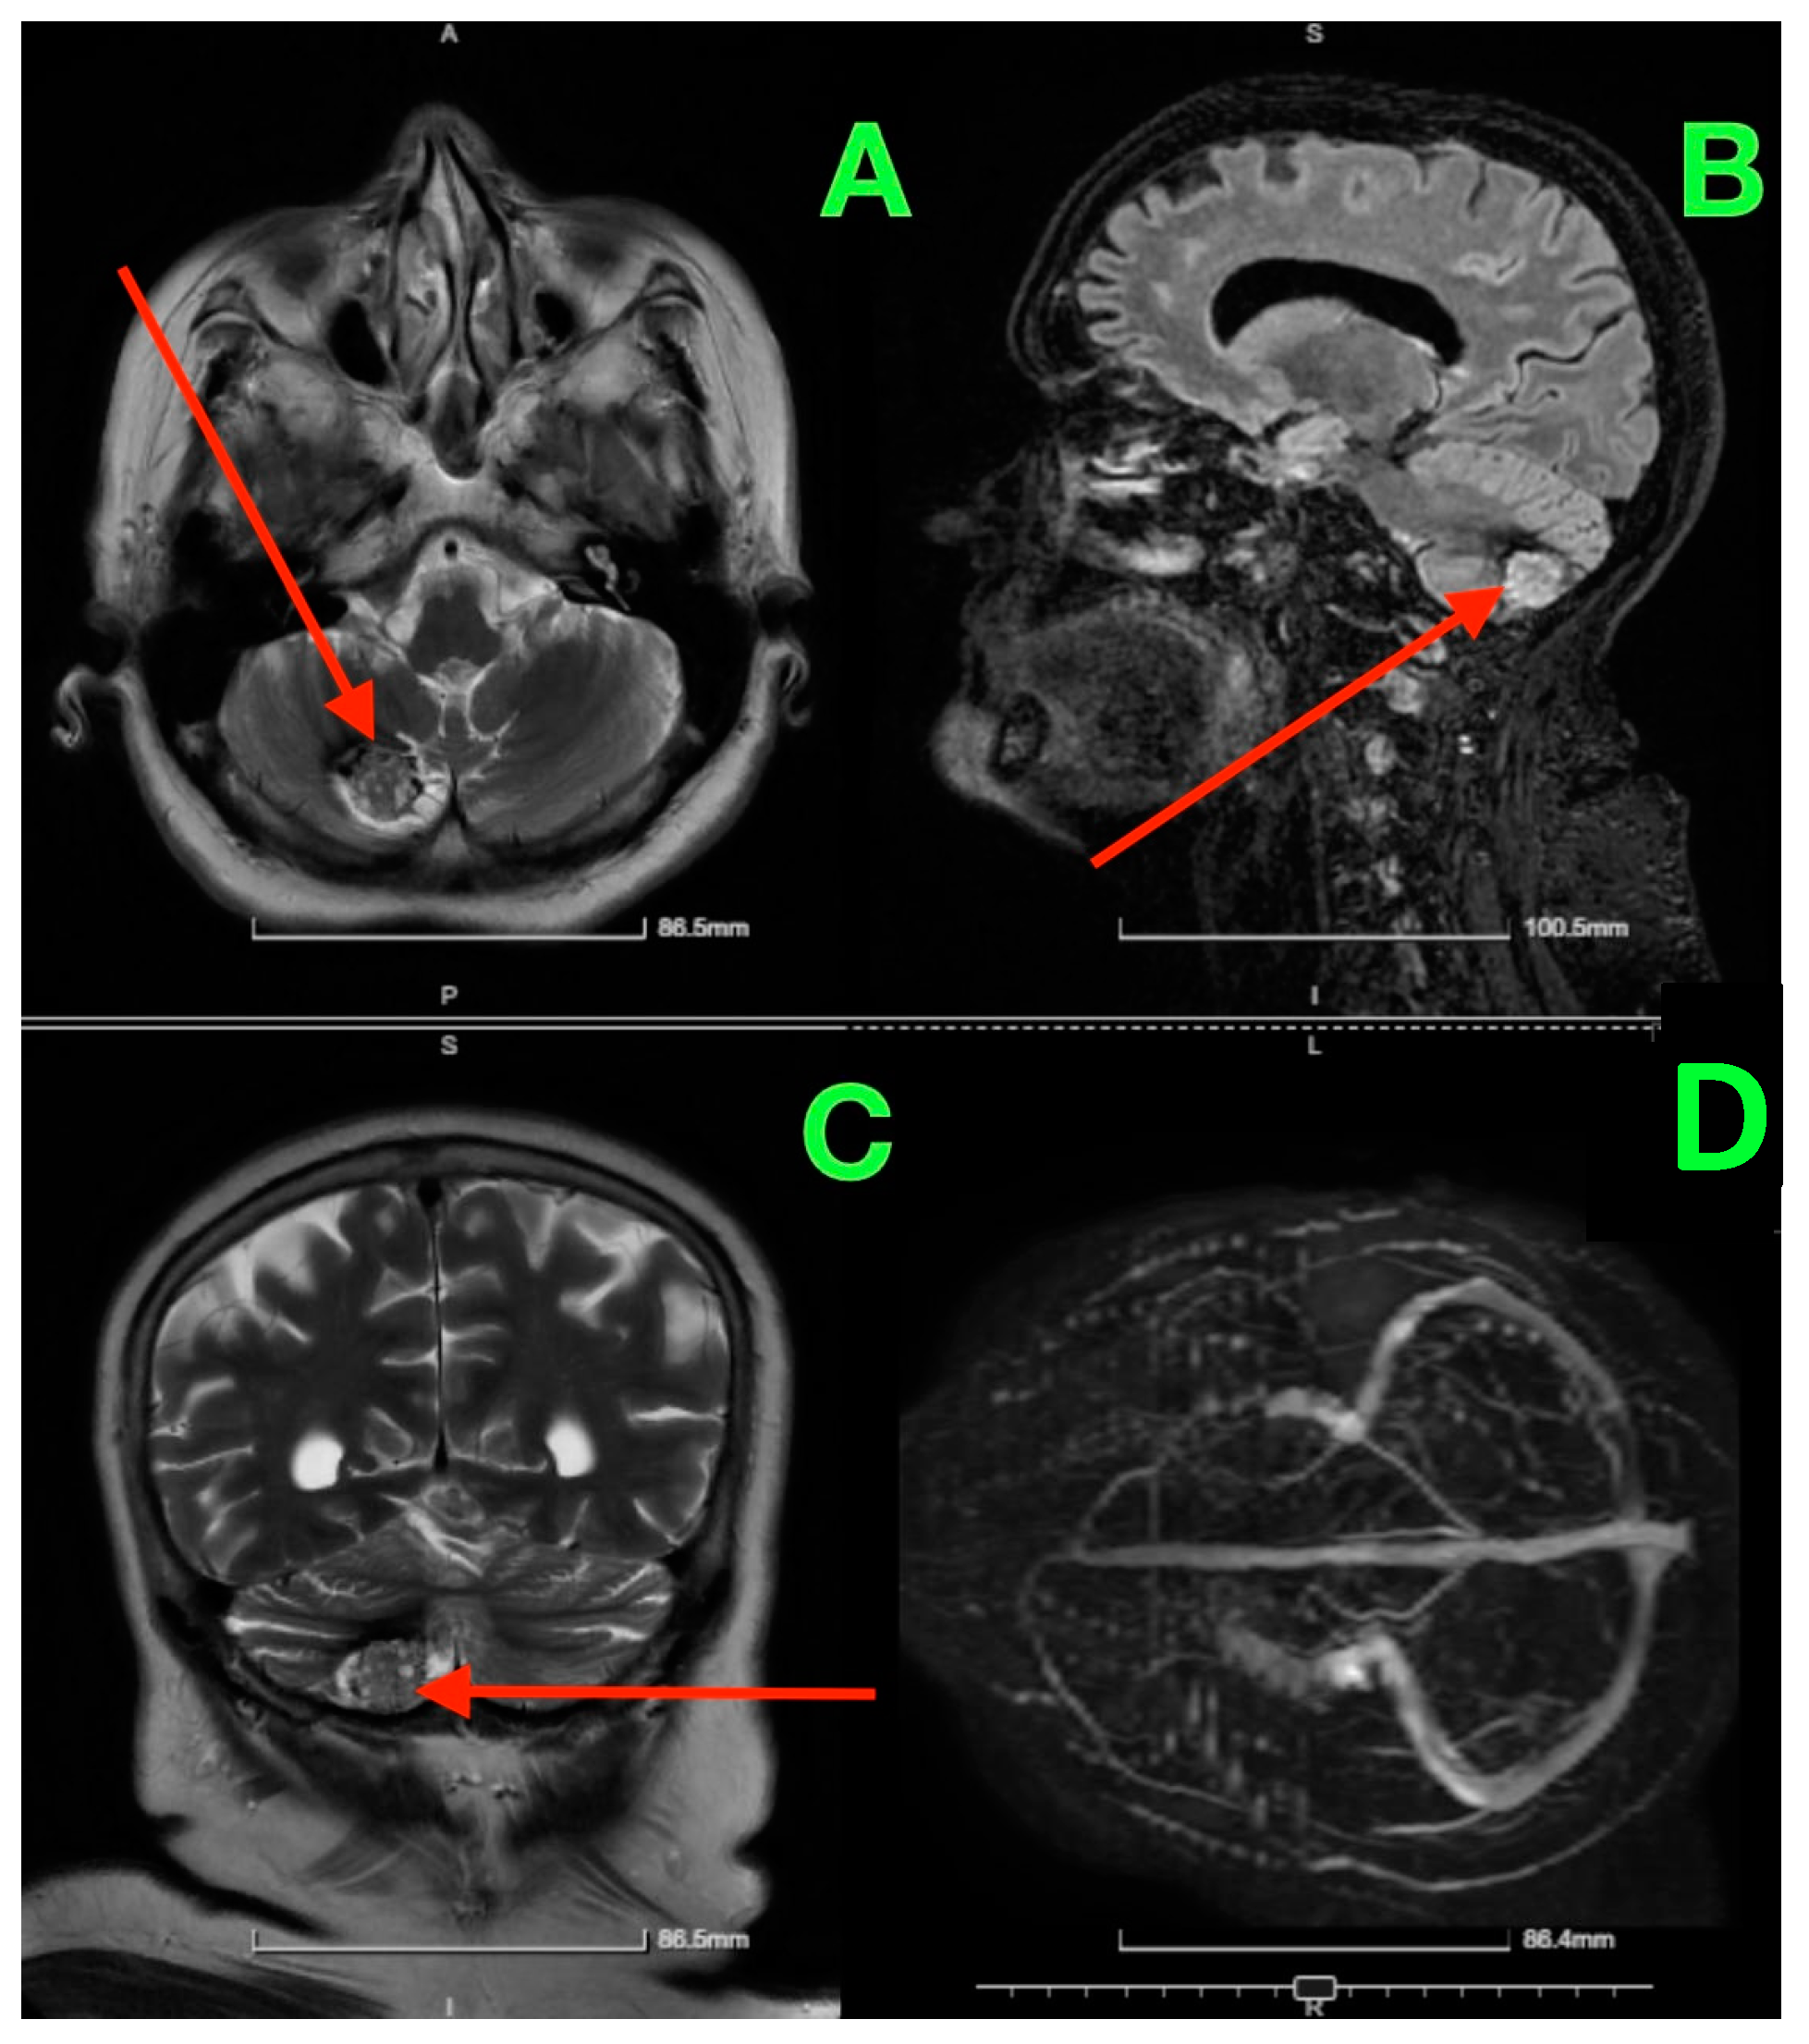

On postoperative day 5, a follow-up CT scan (Figure 3) was performed to assess the surgical site and confirm the absence of postoperative complications such as hemorrhage or hydrocephalus.

Figure 3. Five days post-op CT scan. (A) Demonstrated normal postoperative changes in the right paramedian posterior fossa. The site of the craniectomy was clearly visible, and no signs of residual cavernous malformation were observed. There was no evidence of acute hemorrhage, mass effect, or significant edema in the surrounding cerebellar tissue. Additionally, the ventricular system appeared normal, with no signs of hydrocephalus or midline shift. (B) provided further confirmation of the integrity of the bony structures and the absence of any complications related to the craniectomy. The surgical site remained stable, and there was no abnormal fluid collection or air entrapment within the resection cavity.